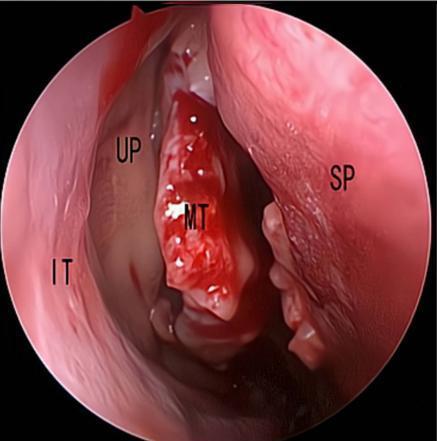

摘要:目的 探究经中鼻甲基板入路的手术技巧及临床效果,旨在系统评估一种兼具良好手术视野和微创性的蝶窦开放径路。方法 回顾性分析2019年9月-2023年9月该院收治的35例孤立性蝶窦病变或单侧蝶窦伴毗邻筛窦受累患者的临床资料,均经中鼻甲基板入路的“四步”程序化操作开放蝶窦。观察手术相关情况和并发症发生情况;采用视觉模拟评分法(VAS)评分,评估头痛和流涕等症状改善情况;采用改良隆德-肯尼迪(MLK)评分,评价术腔恢复状况。结果 所有患者术中保留钩突、中鼻甲和筛泡,26例(74.3%)保留上鼻甲;所有患者均达到临床治愈标准,表现为:术腔引流通畅,黏膜完全上皮化,以及蝶窦开口维持良好开放状态。术后病理显示:蝶窦霉菌病19例(54.3%),蝶窦息肉7例(20.0%),蝶窦黏膜慢性炎症9例(25.7%)。所有患者均未发生严重并发症,仅1例(2.9%)于术后12 d出现中鼻甲创面渗血,经电凝止血后治愈。头痛VAS评分由术前的(4.71±1.66)分,降至术后的(0.83±0.39)分,手术前后比较,差异有统计学意义(t = 13.71,P < 0.01);流涕VAS评分由术前的4.00(0.00,6.00)分,降至术后的0.00(0.00,1.00)分,手术前后比较,差异有统计学意义(Z = -4.47,P < 0.01);手术前后嗅觉减退VAS评分比较,差异无统计学意义(P > 0.05)。MLK评分由术前的4.50(2.00,4.00)分降至1.00(0.00,1.00)分,手术前后比较,差异有统计学意义(Z = -5.20,P < 0.01)。结论 经中鼻甲基板入路蝶窦开放术,严格遵循鼻窦解剖层次,在最大限度地保留鼻腔生理结构的前提下,可获得理想的术野暴露。该术式对于局限于蝶窦及后组筛窦的病变,具有确切的临床疗效。值得应用于临床。